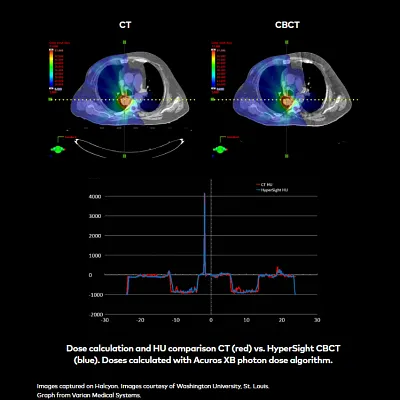

"The new HyperSight imaging solution on Halcyon offers improved image quality with CT number accuracy comparable to planning CT, which may lead to improved dose calculation accuracy. HyperSight may allow for treatment planning directly on a CBCT image in an adaptive workflow."

Taasti et al., Clinical evaluation of CT number stability of advanced cone-beam CT for thorax and pelvic patients, Maastro. ESTRO 2024.